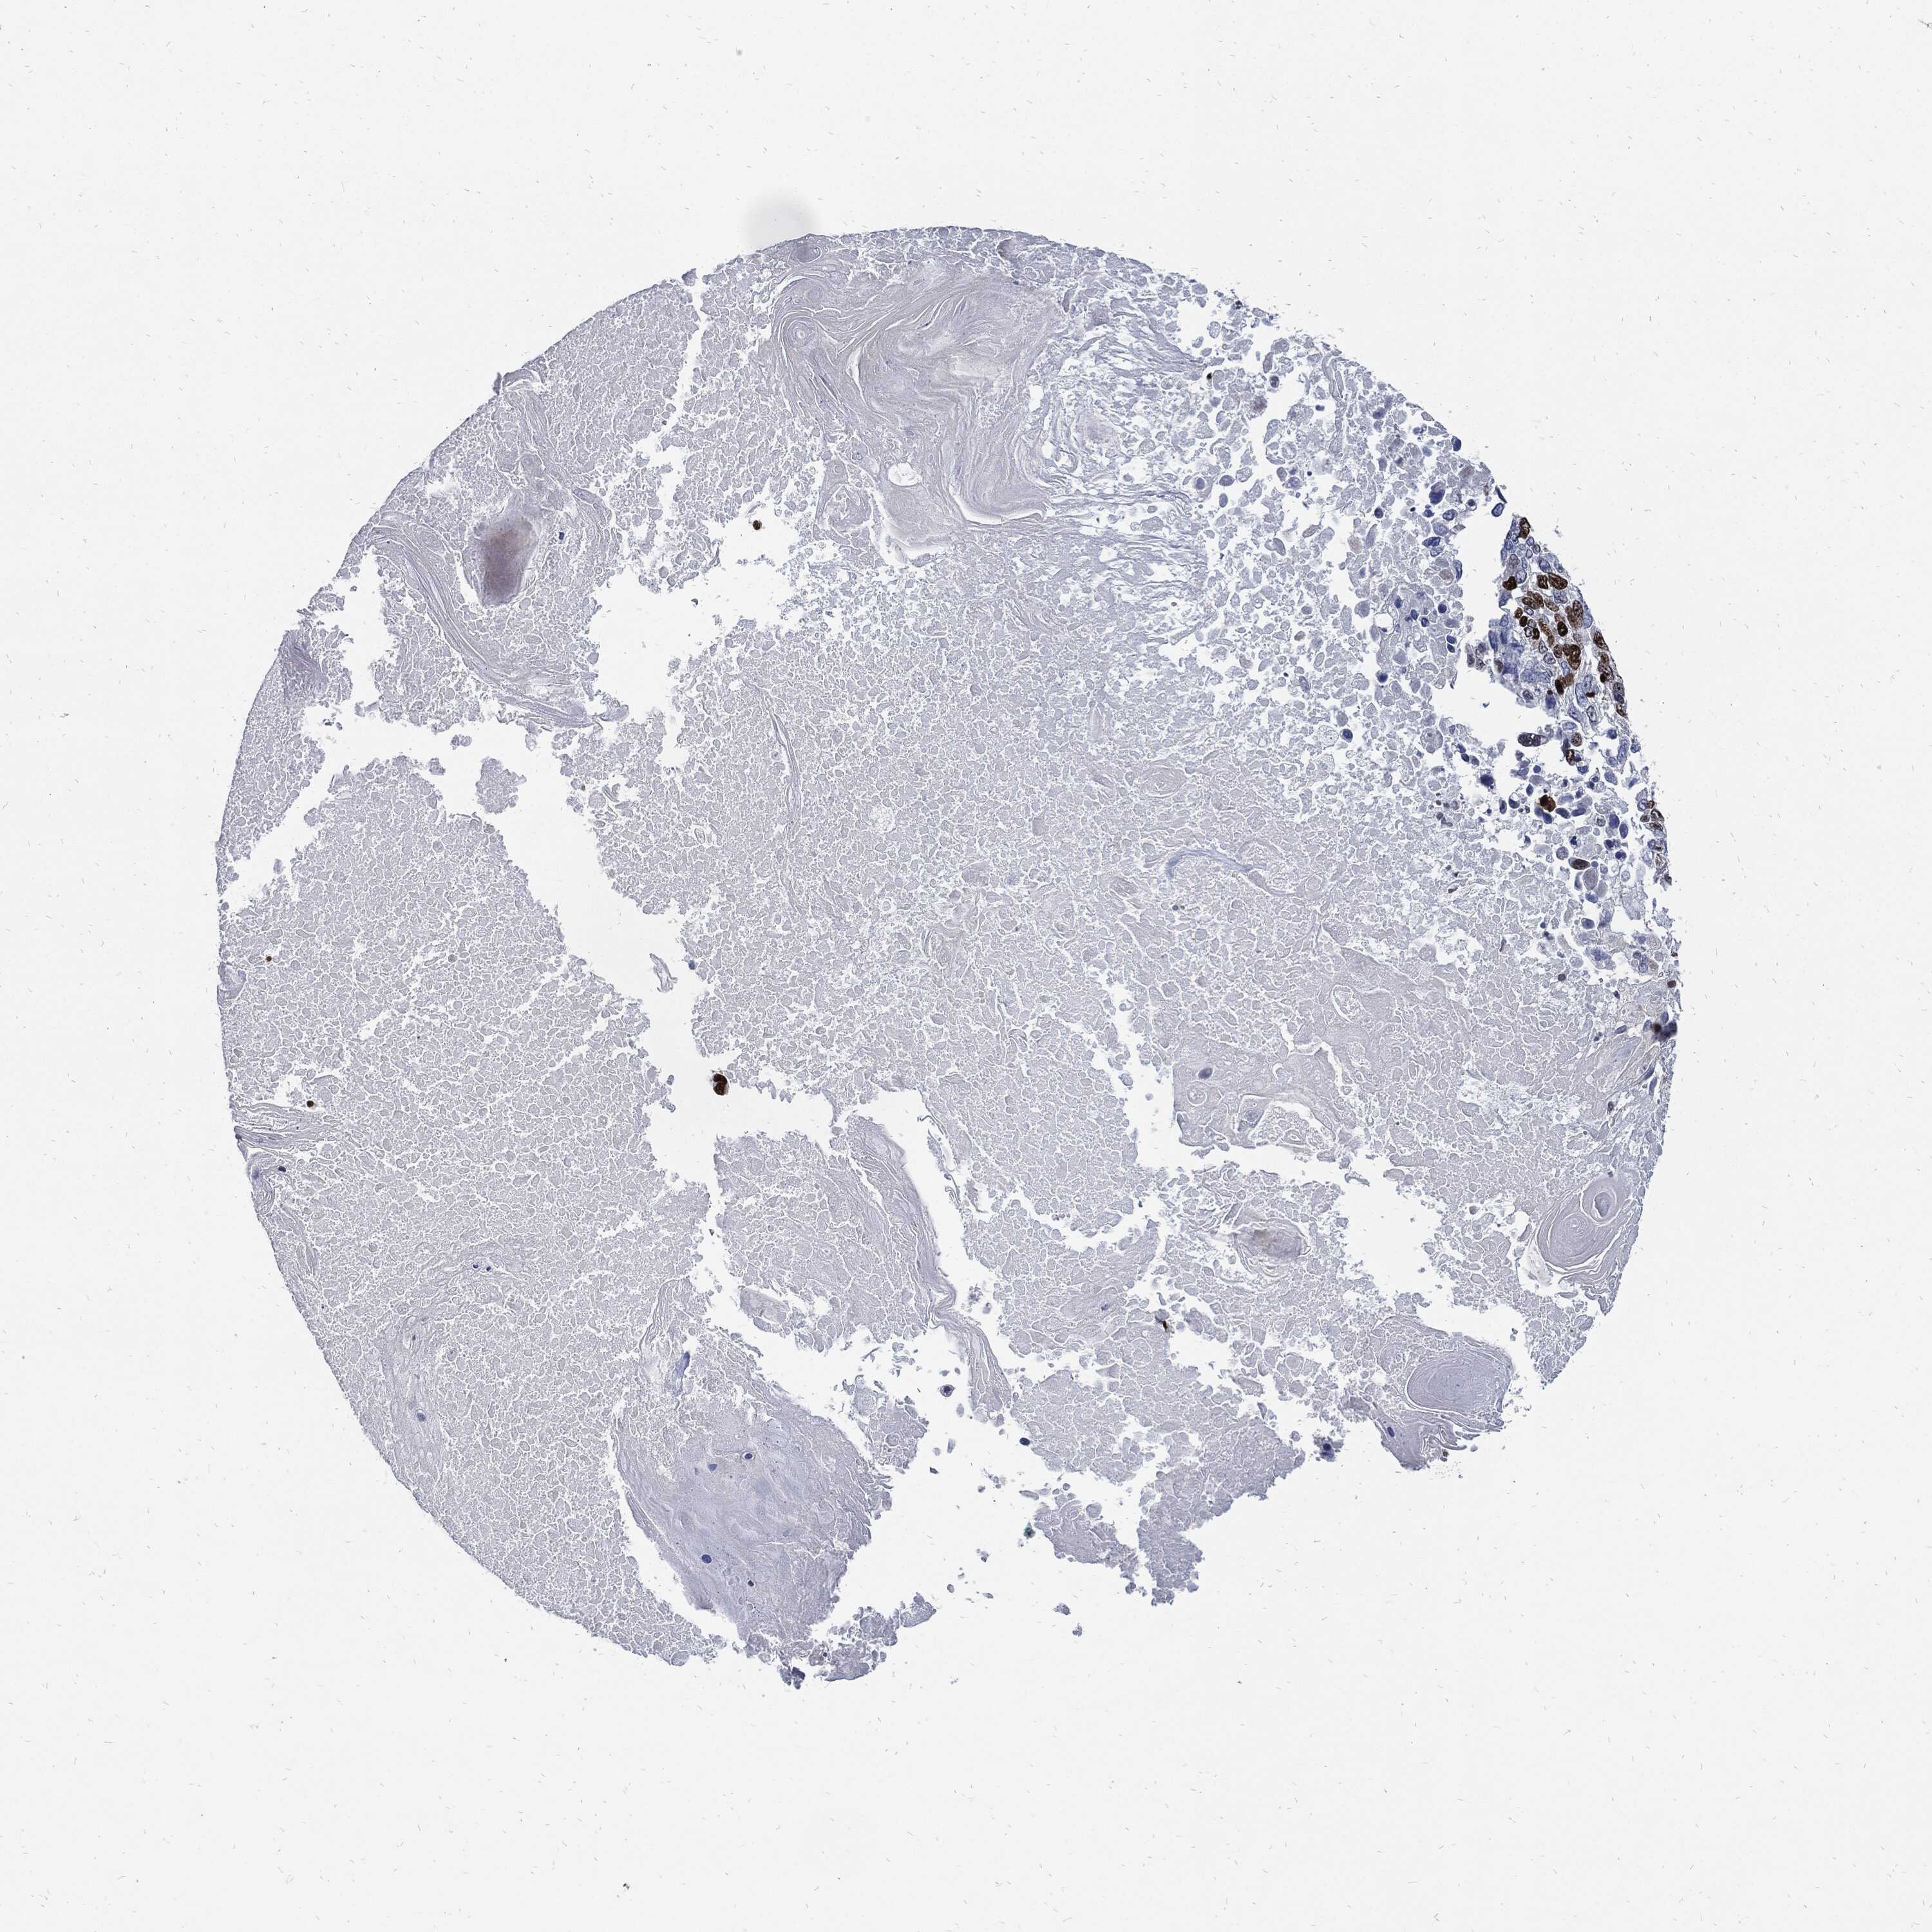

LUNG SQUAMOUS CELL CARCINOMA (TCGA) - Interactive survival scatter ploti

MKI67 is not prognostic in Lung Squamous Cell Carcinoma (TCGA)

: 13.48

Average pTPM 15.6

Number of samples 489